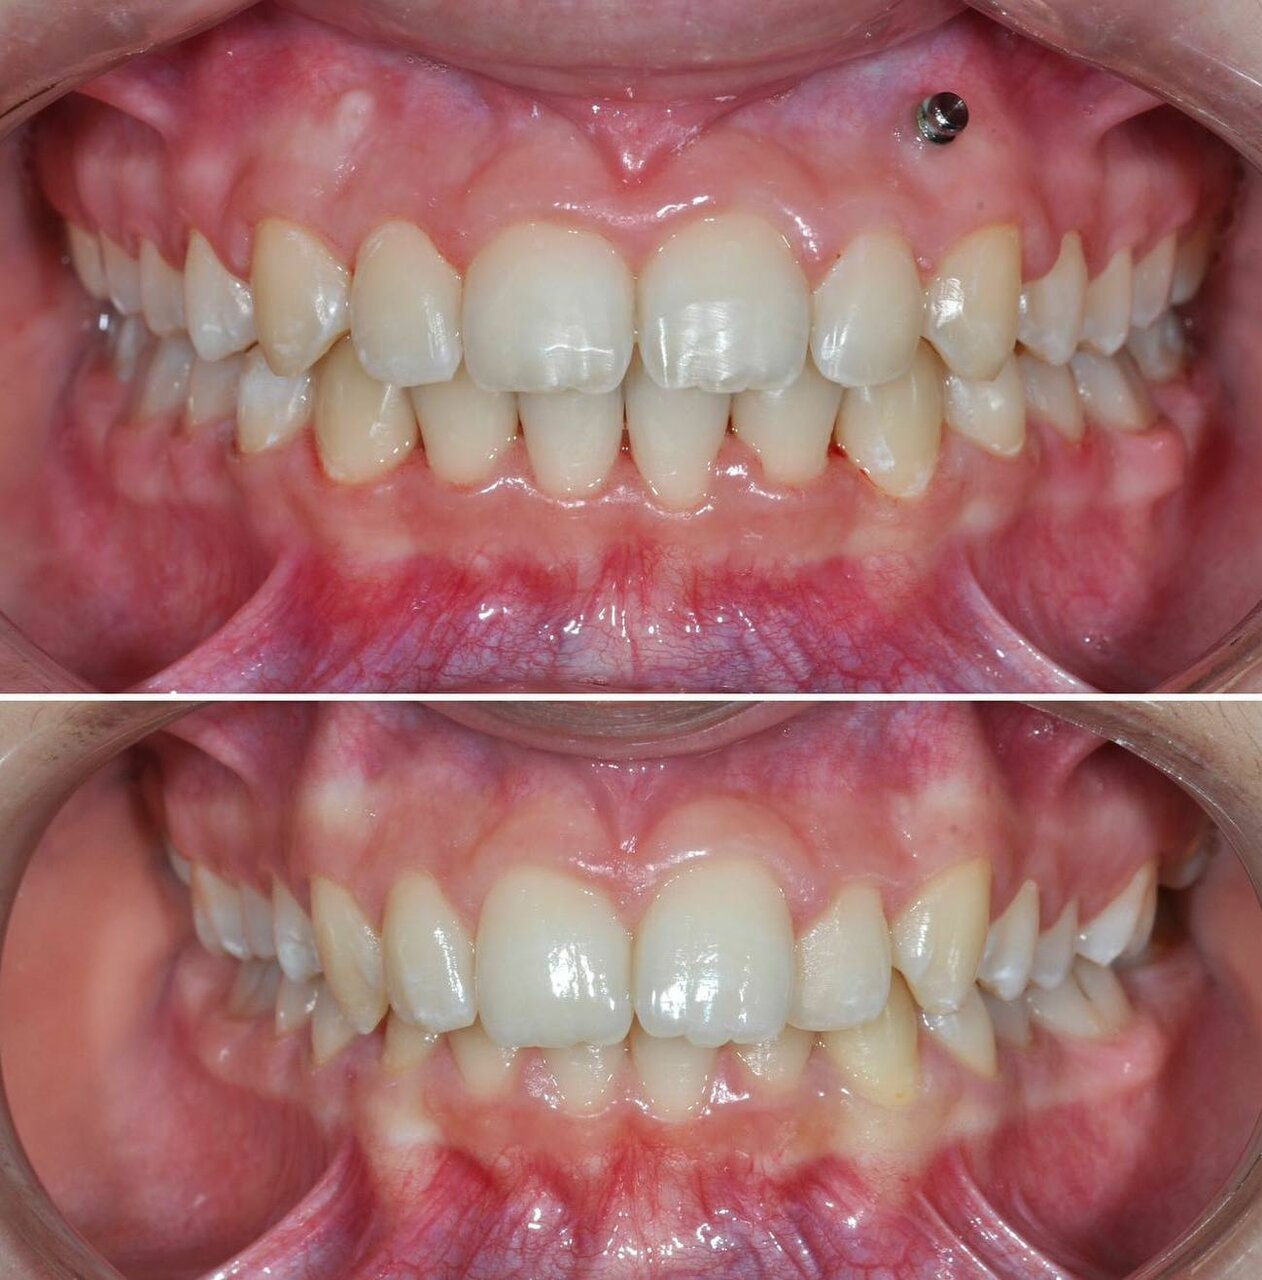

Клиника предоставляет услуги по всем основным направлениям стоматологии, включая общую стоматологию, ортодонтию, хирургическую и эстетическую стоматологию, а также детскую стоматологию. Среди дополнительных услуг: лечение кариеса, пломбирование, удаление зубов, имплантация, протезирование, отбеливание, установка виниров и брекетов, лечение десен и каналов, рентгенография, челюстно-лицевая хирургия и френулопластика.

Записывался на консультацию и дальнейшую установку брекетов для исправления прикуса. Впечатления на данный момент только положительные. Работа аккуратная, отношение вежливое, дополнительных услуг не навязывали.